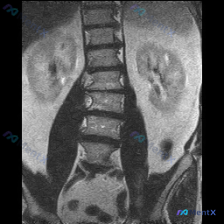

整理到一个有意思的影像观察讨论素材: - 有一份腹部MRI-T2冠状位影像 - 影像科正式报告的结论是:双侧肾脏形态信号正常,未见腹腔积液及明确占位;腰椎椎体形态及信号未见明显异常 - 但观察者在看片时,直观觉得脊柱冠状面的排列“有点不对”,怀疑存在脊柱侧弯 目前没有提供患者的年龄、性别、症状或查体...